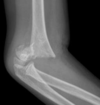

Normal XR elbow

**Colles - ‘dinner fork type deformity’** Features of the injury 1. Transverse fracture of the radius 2. 1 inch proximal to the radio-carpal joint 3. Dorsal displacement and angulation of the distal radius